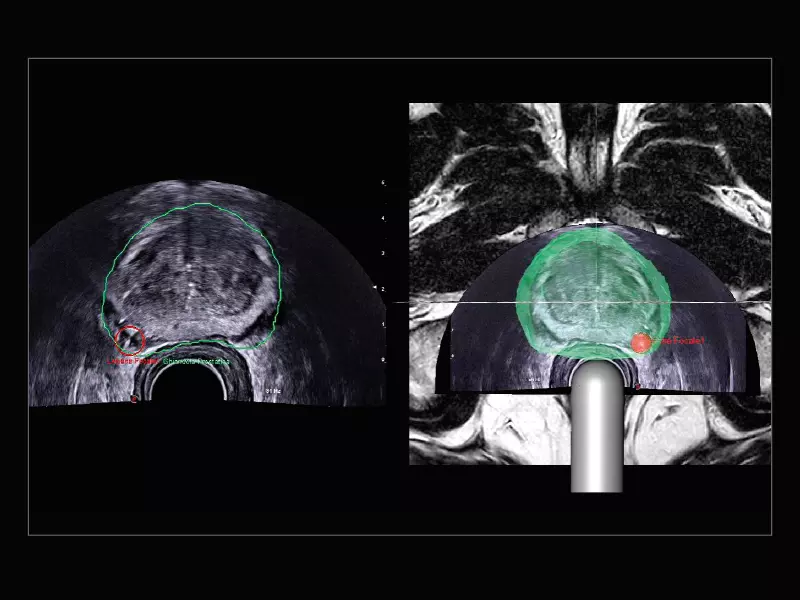

MyLab™E80 - Urofusion - TP Biopsy

MyLab™E80 - Urofusion - TP Biopsy

MyLab™E80 - Urofusion - Systematic Biopsy Guide

MyLab™E80 - Urofusion - Systematic Biopsy Guide